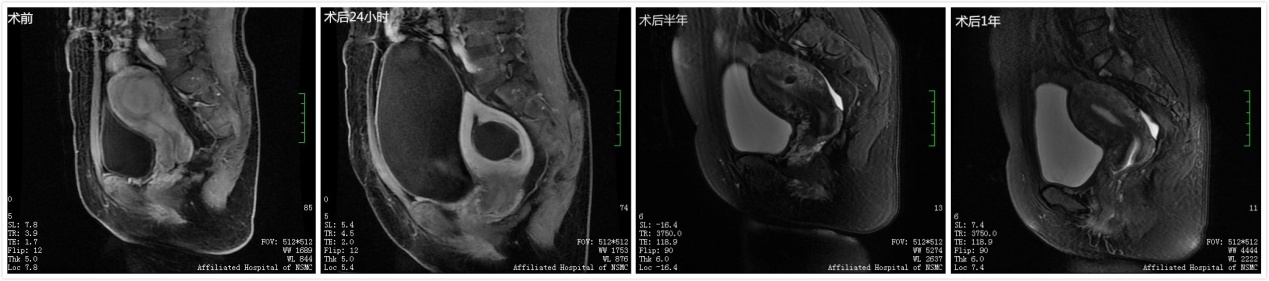

子宫肌瘤患者,女,46岁,超声消融治疗前、治疗后24小时、半年、1年MRI显示:超声消融治疗后子宫肌瘤完全坏死,组织吸收。